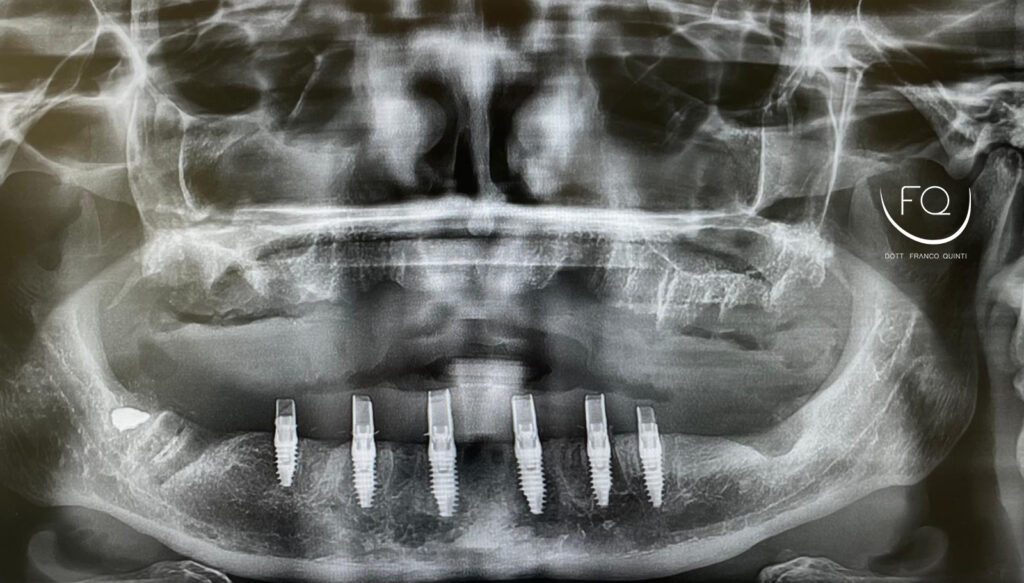

L’intervento è stato eseguito mediante chirurgia implantare tradizionale: dopo la bonifica e l’osteotomia della cresta alveolare sono stati inseriti 6 impianti PRAMA di Sweden & Martina da 3,8 x 10 e 3,8 x 11,5.